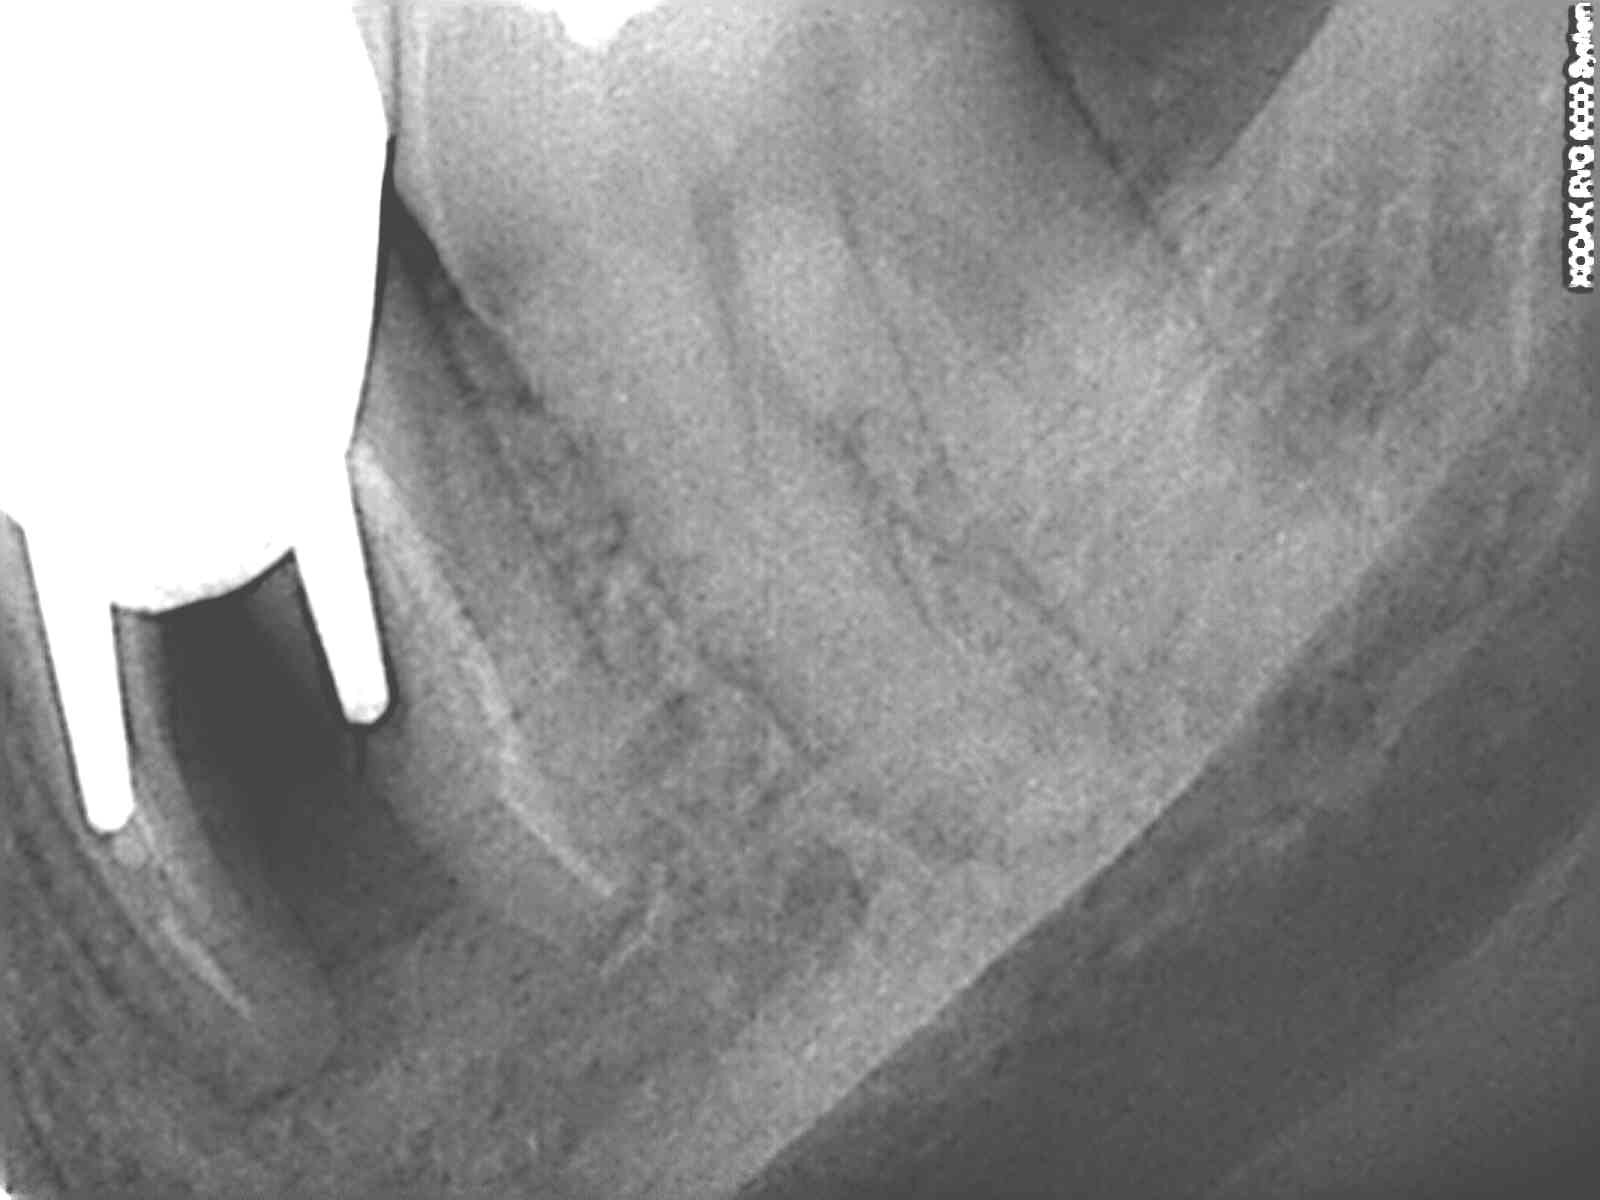

C'est pourquoi dans ce cas avec une furcation de classe 3 j'ai choisi la conservation de la 26 en me laissant donc la possibilité d'implanter dans quelques années si besoin.

Pour ceux d'entre nous qui ont été formés en paro avant la généralisation de l'implantologie, le TT conservateur de choix des lésions inter-radiculaires de cl 3 au maxillaire était l'amputation radiculaire à la condition expresse que l'anatomie du tronc radiculaire cervical se prête à une élimination complète de la plaque. Evidemment, sous lambeau muco-périosté avec une plastie cervicale visant à éliminer tout ressaut ou bombé résiduel. Si ces conditions sont remplies, les pronostics étaient plutôt bons. En général on préfère virer la rac DV que la MV... ensuite tout dépend de l'endo bien sur... faut être sur qu'il n'y a pas un MV2 oublié qui va fiche le bazar à court terme... car bien sur si ça évolue en lésion endo paro, sur le plan osseux c'est le désastre.

Pour ceux qui doutent de la maintenance, avec un fil et des brossettes on fait des merveilles! Suivi par recall à 6 mois.